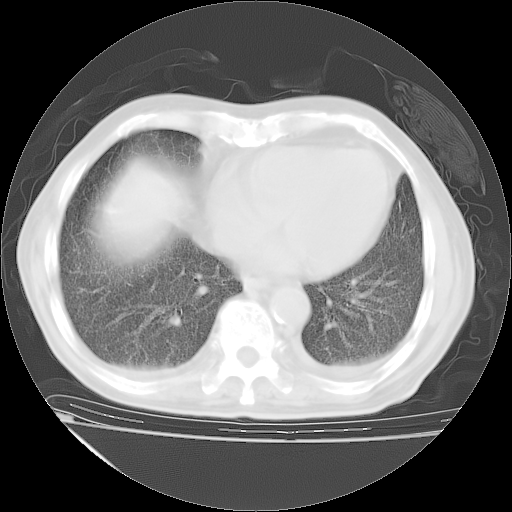

经过24天治疗,岳父的病情基本稳定。生活基本可以自理,可以下床活动。呼吸困难早已消失。体温基本正常。

只是甲强龙用80mg时血小板升到正常,改为60mg后又降到63×10*9/L。

主要治疗甲强龙80mg×14天,60mg×10天;同时抗结核(异烟肼+利福平+乙胺丁醇)。环磷酰胺0.1 tid 10天。

特别感谢胡教授、高管、桃子版主给出关键的治疗建议。桃版把所有肺部影像和全部临床资料请所在医院呼吸科、感染病科、结核科、临床免疫科专家会诊。临床免疫科专家制定了完整的治疗方案。